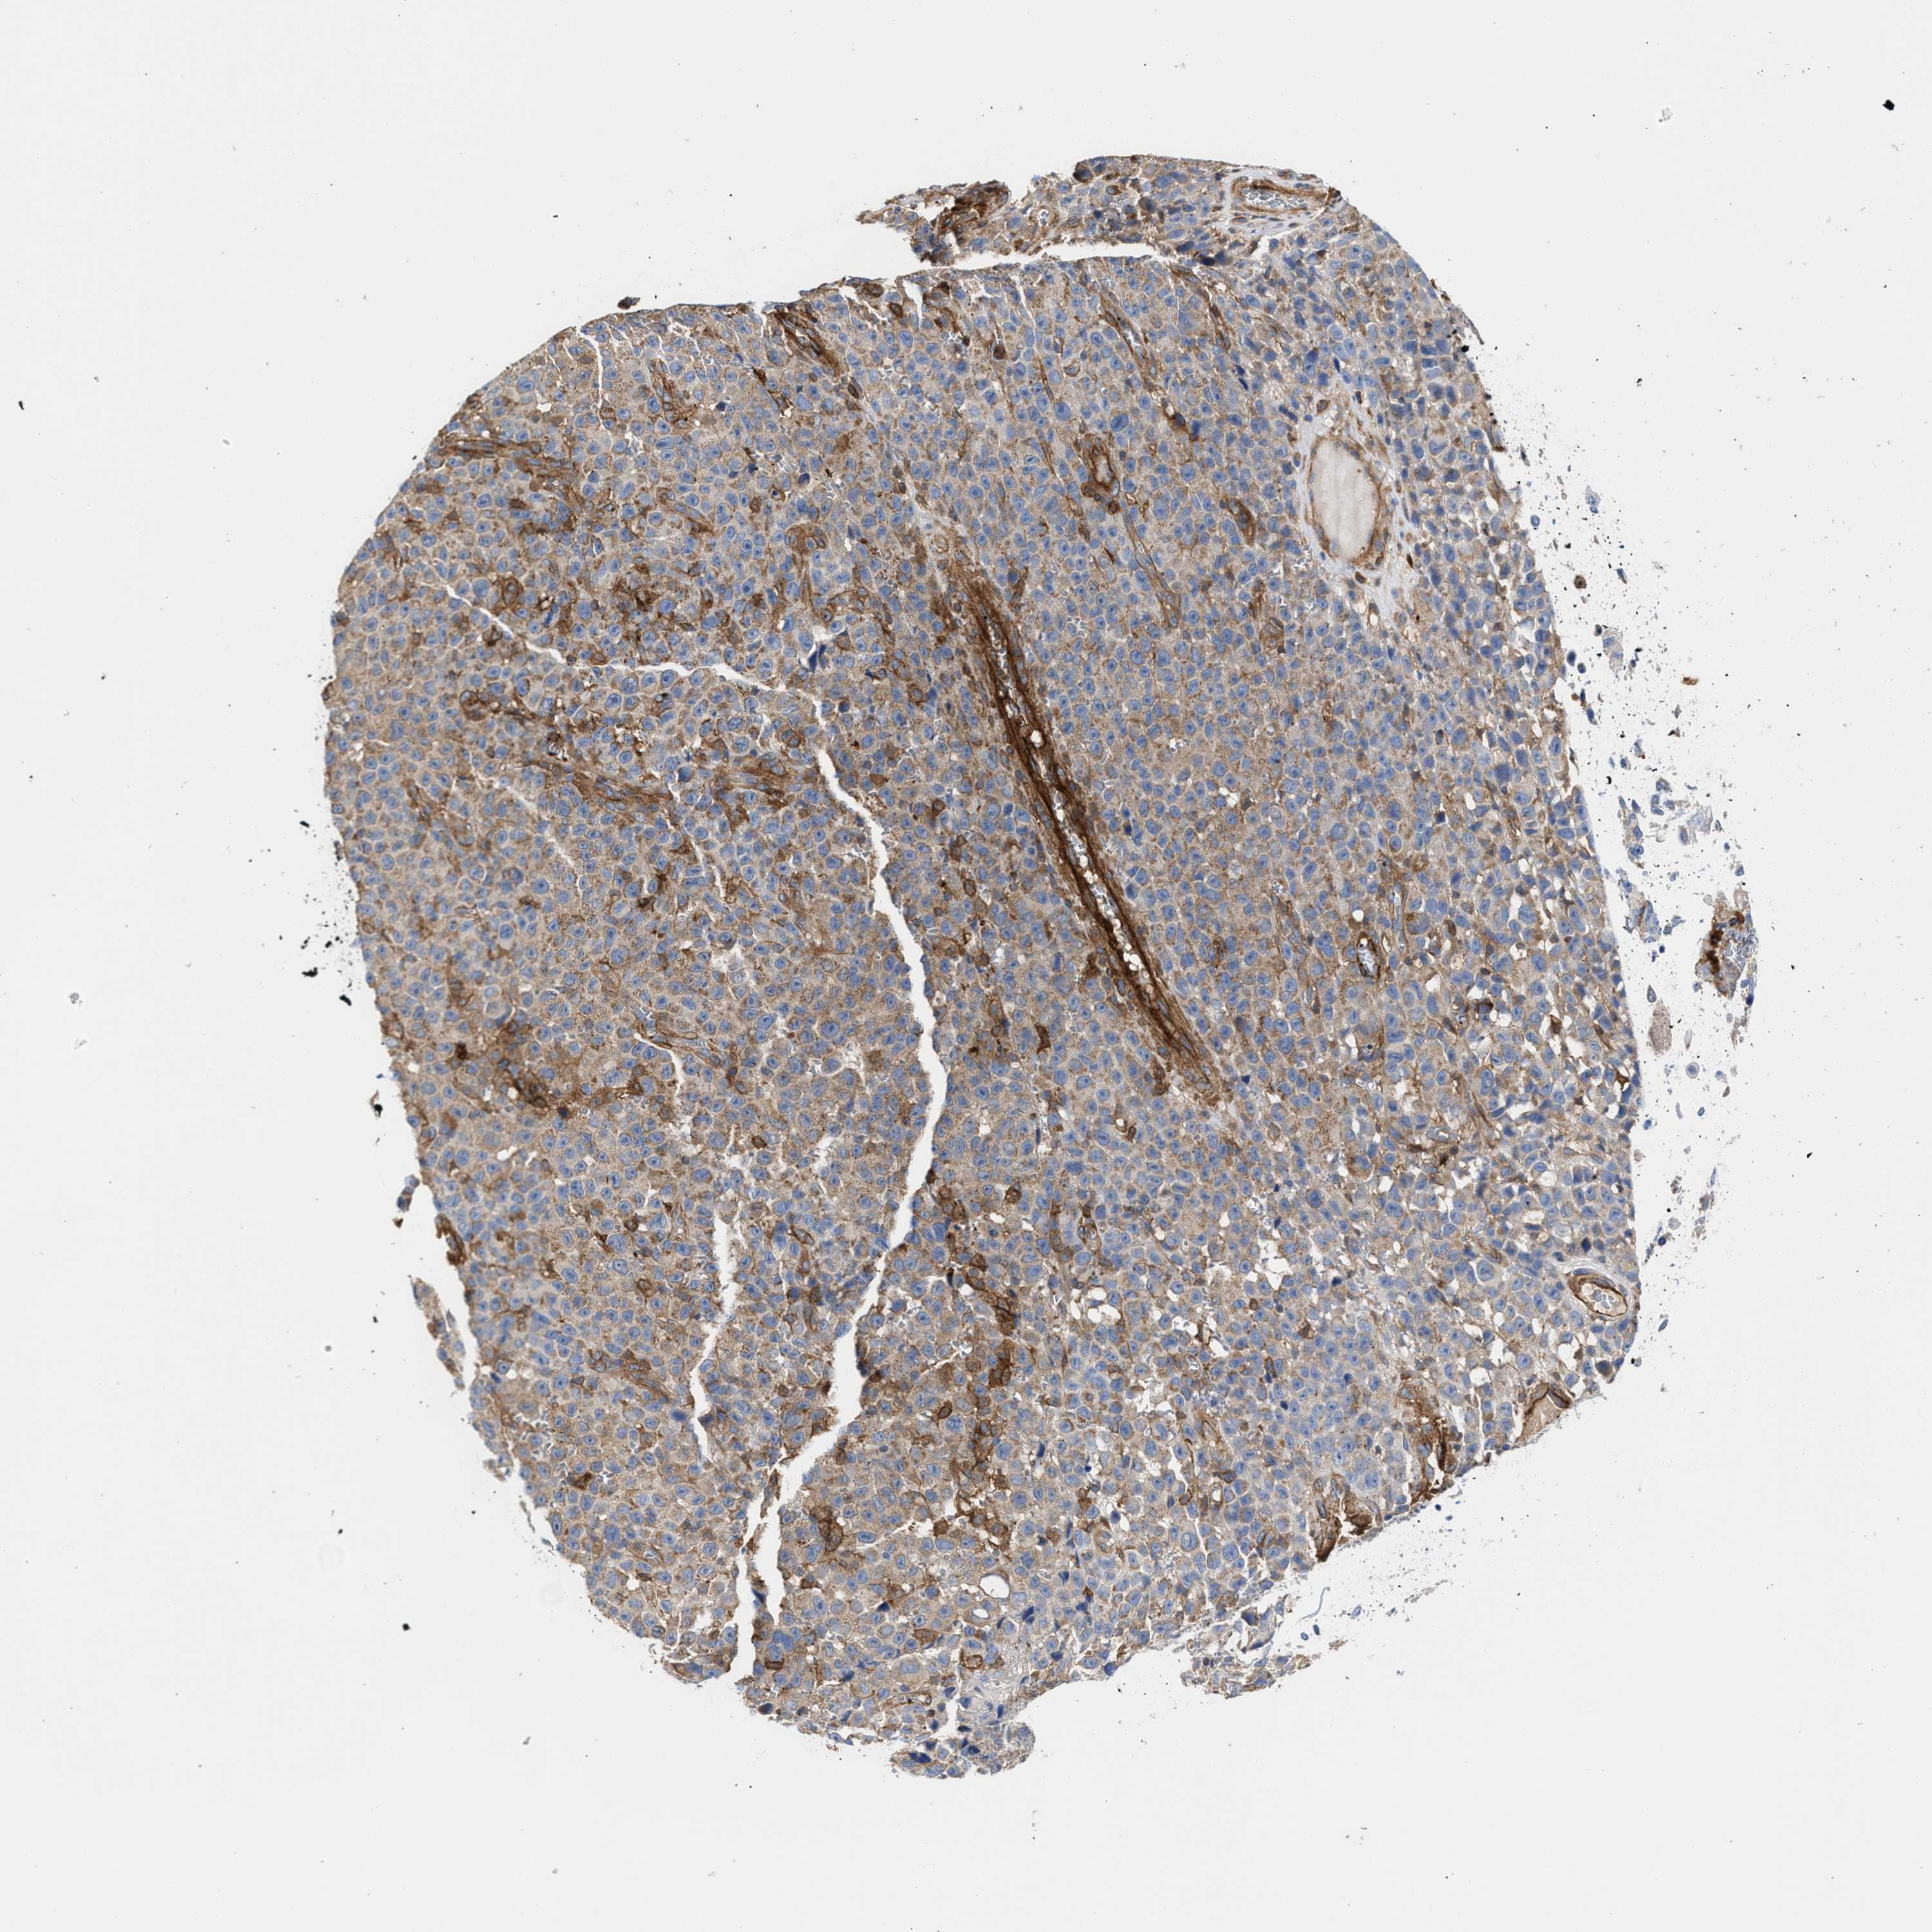

SKIN CANCER - Protein expressioni

A mouse-over function shows sample information and annotation data. Click on an image to view it in a full screen mode. Samples can be filtered based on level of antibody staining by selecting one or several of the following categories: high, medium, low and not detected. The assay and annotation is described here.

Antibody stainingi

Antibody staining in the annotated cell types in the current human tissue is reported as not detected, low, medium, or high, based on conventional immunohistochemistry profiling in selected tissues. This score is based on the combination of the staining intensity and fraction of stained cells.

Each image is clickable and will lead to virtual microscopy that enables deeper exploration of all samples and also displays staining intensity scores, fraction scores and subcellular localization as well as patient and tissue information for each sample.

Antibody HPA021823

Basal cell carcinoma

Squamous cell carcinoma, NOS

Squamous cell carcinoma, metastatic, NOS

BCC, high aggressive